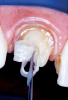

Fig 6. After a dual-cured composite resin cement is injected into the post channel, the reinforcement fiber is placed to the base of the post channel, and the ends of the fiber are folded back into the channel and arranged into the desired shape of the core and light-cured for 60 seconds (Fig 6). A dual-cured or light-cured composite is injected over the coronal fibers, and the composite material is adapted, sculpted, and smoothed with a No. 2 sable brush into the desired form and dimension of an ideal preparation (Fig 7).

Figure 6